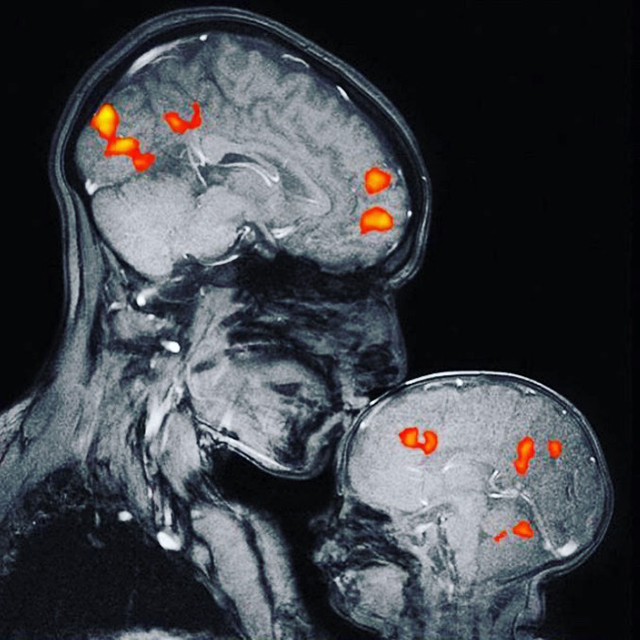

U najnovijoj studiji, u kojoj je učestvovalo više od 140 mališana i beba, naučnici su, skeniranjem mozga , pokazali da su regije za obradu jezika kod neke djece imali veću koncentraciju mijelina – izolacionog omotača koji okružuje neurone i omogućava im da šalju poruke brže i efikasnije. Ne zna se da li taj dodatni mijelin zapravo utiče na jezičke sposobnosti dvoipogodišnjeg djeteta, ali istraživači misle da bi to moglo da stvori neke prednosti, prenosi magazin Science alert.

U hiljadama sati prikupljenih audio zapisa, istraživači su mogli da čuju šta djeca čuju svakog dana. Zatim je tim odabrao nešto više od polovine djece, kojima je snimljena glava na magnetnoj rezonanci tokom sna kako bi se vidio nivo milenijalizacije. Među šestomjesečnim bebama, više priče na dnevnoj bazi povezano je sa manjom mijelinizacijom, što predstavlja suprotan rezultat od onoga što je pronađeno kod dvije godine starije djece.

Samo nekoliko sati nakon rođenja, mozak bebe pokazuje znake da već uči zvukove jezika. A “bebeći govor” koji odrasli koriste kada pričaju sa svojim najmlađim članovima, dugoročno će dovesti do boljih jezičkih veština. Prethodne studije su čak otkrile da se kod djece u uzrastu od četiri do šest godina, a koja više razgovoraju sa odraslima, otkrila veća mijelinizacija u regionima mozga koji su povezani sa jezikom. Nova otkrića pokazuju da se sličan efekat pojavljuje i kod mlađe djece.